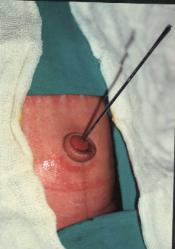

FOTO No 3: OMBLIGO, FISTULA,

ARTERIAS UMBILICALES SECCIONADAS

Y VEJIGA

preoperatorios de rutina fueron normales. Se programo la intervención quirúrgica, realizándose una

laparotomía exploradora, con una incisión semicircular infraumbilical y media infraumbilical hasta 2 CMS del

pubis. Previa disección del granuloma umbilical, separándolo de la piel, se encuentra una FÍSTULA

UMBILICOVESICAL u ONFALOVESICAL (foto 2,3,4)(Fig. 4E), de 2.5 CMS de longitud, una

comunicación directa del ombligo a la vejiga urinaria, en forma de embudo, observándose que la vejiga

estaba directamente por detrás del ombligo, nunca había descendido. Se procede a resecar la fístula, con

ligadura transfictiva de material no reabsorbible, asimismo se ligan con material no reabsorbible las dos

arterias umbilicales obliteradas(hipogástricas)(foto 3). Igualmente se realizo hernioplastia umbilical. Se manejo